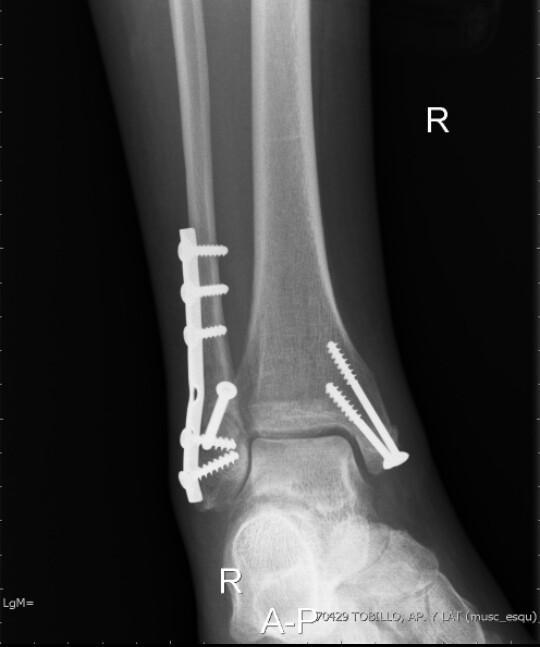

Fractura Maleolo Peroneo Sin Desplazamiento, MALÉOLO PERONEO | Qué es, significado, ubicación, función y lesiones, 4.03 MB, 02:56, 12,945, FisioOnline, 2020-12-15T19:13:43.000000Z, 3, Do You Need an Ankle X-Ray? - Therapydia Portland, therapydiaportland.com, 2000 x 905, jpeg, WebLa fractura del tobillo es una lesión relativamente frecuente. Se caracteriza por la ruptura de la prominencia ósea en la parte externa (tercio distal del. WebFractura no desplazada maléolo peroneo D Mi hija el día 03-03-12 se fracturo el maléolo peroneo sin desplazamiento y el han puesto una férula suropédica. Le estamos., 20, fractura-maleolo-peroneo-sin-desplazamiento, Novedades y Muebles WebLa fractura del tobillo es una lesión relativamente frecuente. Se caracteriza por la ruptura de la prominencia ósea en la parte externa (tercio distal del. WebFractura no desplazada maléolo peroneo D Mi hija el día 03-03-12 se fracturo el maléolo peroneo sin desplazamiento y el han puesto una férula suropédica. Le estamos.

WebAsumiendo que se trata de una fractura no quirúrgica, hay que mantener el tobillo inmovilizado, en descarga y con yeso hasta que se produzca la consolidación de la. WebLas fracturas de tobillo son una de las fracturas más comunes de las extremidades inferiores y alrededor del 9% de todas las fracturas. A veces, el maléolo.

WebAnatomía interactiva. El tobillo está conformado por diferentes zonas anatómicas esenciales para que podamos caminar y desplazarnos. Existen dos zonas prominentes en el tobillo. WebLa fractura puede desplazarse, si es el caso, debe corregirse quirúrgicamente. Pseudoartrosis, esto significa que aún no existe una conexión ósea estable entre los. WebLas fracturas de tobillo se producen en el maléolo medial o posterior de la tibia y/o el maléolo lateral del peroné. Estas fracturas pueden ser estables o inestables.. WebUna fractura se puede clasificar según la ubicación de los fragmentos óseos en: Compuesto: tras la fractura, los fragmentos óseos no sufren desplazamientos con. WebEn esas fracturas se recomienda no cargar la pierna 4-6 semanas. Aunque el mayor riesgo de desplazamiento se produce en las 3 primeras semanas, es posible que se haya. WebEl tiempo de recuperación de una fractura de maleolo peroneal sin desplazamiento suele ser de entre 6 a 12 semanas. ¿Cuánto tarda en curar una fractura de maleolo externo? A. WebFractura del maléolo externo del peroné sin desplazamiento apoyar pie. El 15/11/2013 hace hoy 16 días me fracturé el maléolo externo del peroné sin deplazamiento. Me.